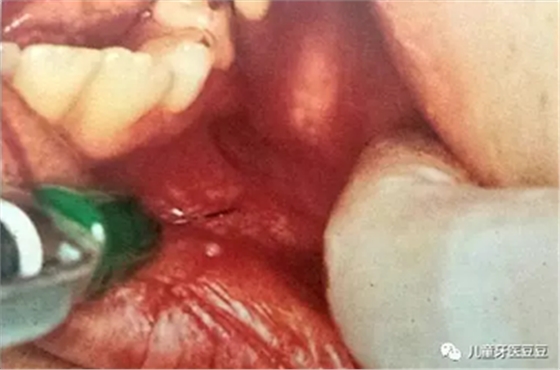

如果孩子在牙科治療中有過疼痛的經(jīng)歷,將會對他們將來一生的口腔治療產(chǎn)生影響,因此每次治療的時候應(yīng)將不適感降到最小,做到這點(diǎn)最有效的方法就是采用局部麻醉。

有些家長擔(dān)心麻醉會不會影響到孩子的大腦。其實(shí)兒童治療中常采用表面麻醉,浸潤麻醉和傳導(dǎo)麻醉,這些麻醉方法都是局部麻醉,主要作用于局部的牙齒、黏膜、骨,很少進(jìn)入血液,也自然對全身(包括大腦)影響很小。而且有經(jīng)驗(yàn)的醫(yī)生也會采用分散孩子注意力的方法讓孩子對局部麻醉注射的恐懼降到最低。

口腔局部浸潤麻醉